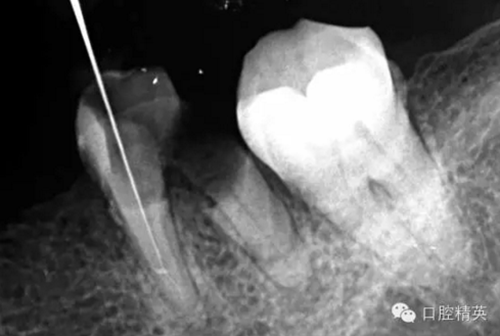

近中舌根疏通,兩根分離的器械都在近中舌根。花費(fèi)2個(gè)多小時(shí)。將它疏通下去還是離不開較長的時(shí)間,也就是耐心,它真的很重要哦!~第二個(gè)我覺得器械分離的疏通,就是在于能否建立旁路,那么怎么去建立這條路。我個(gè)人覺得首先挫的選擇,是k挫,是c+,還是別的什么。我的首選是8號(hào)c+,因?yàn)樗鼔蛴玻?號(hào)的k挫太軟,沒有辦法擴(kuò)下去,很容易碰到根內(nèi)部器械導(dǎo)致器械報(bào)廢,尖端變光亮。但是c+挫也不是那么完美,我擴(kuò)的時(shí)候用了4根8號(hào)新的c+挫,全部報(bào)廢。尖端彎曲90度的,有變成麻花的。這些都在提醒我可能用力過大,或者根管內(nèi)部太過于復(fù)雜。疏通時(shí)只有慢慢來,一點(diǎn)點(diǎn)的下千萬不要妄想一步到位。手法還是要輕柔否則你的器械一樣也會(huì)分離進(jìn)去。疏通到挎自己的器械的時(shí)候也是碰到分離的器械時(shí),這個(gè)時(shí)候最好是上下提拉,切勿旋轉(zhuǎn)向下,你只有盡量將該部位擴(kuò)開,為下一步往下疏通留有足夠的空間就好。而不是繼續(xù)向下旋轉(zhuǎn),這樣會(huì)導(dǎo)致器械的分離,加大你疏通的難度。